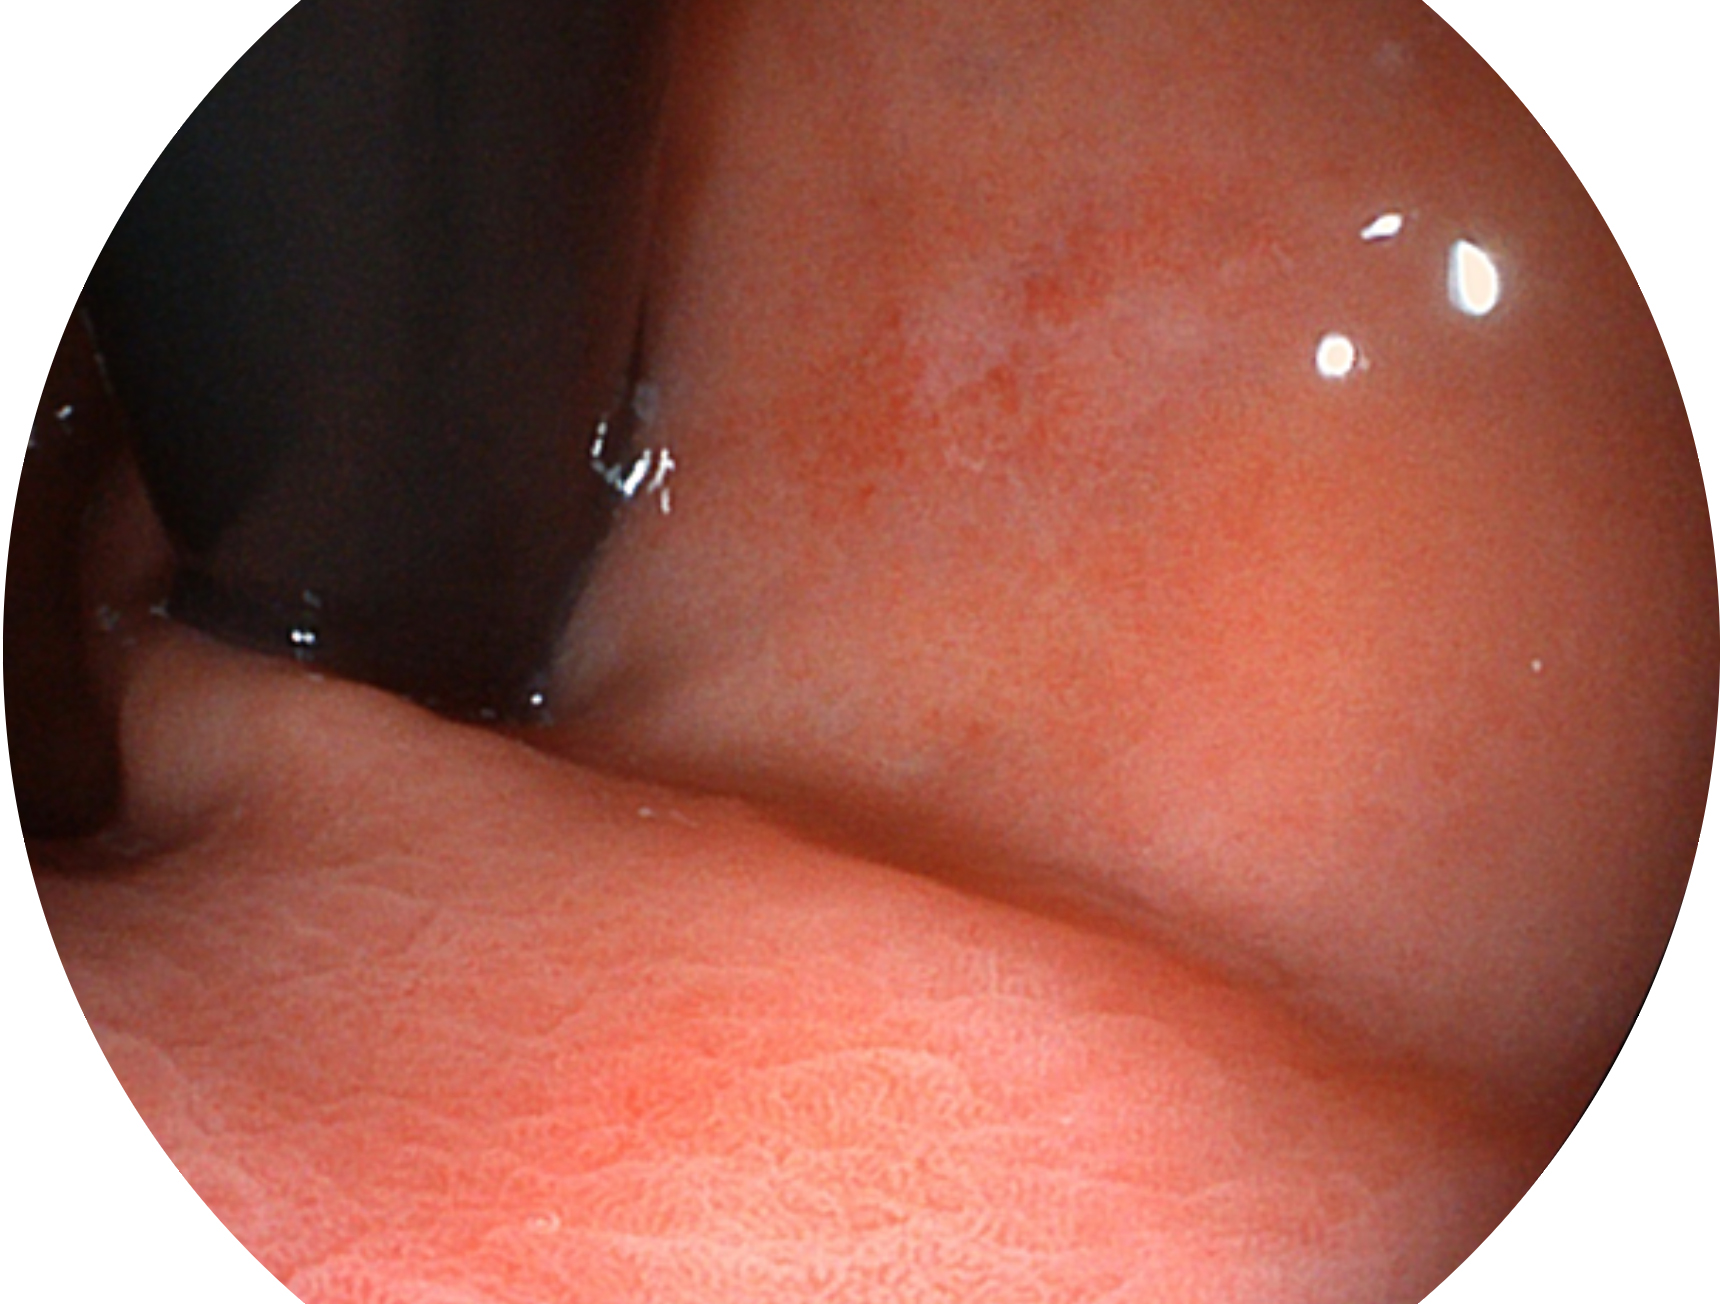

云顶集团官网新开发的内镜染色技术,主要是基于多波长LED 光源的开发,VLS-55Q 四波长LED 光源是由四个不同颜色的LED光按照相应照明模式所规定的特定发光比例进行合束后形成,合束后形成的照明光的光谱由红光、绿光、蓝光及蓝紫光这四个不同的波段范围构成。具有更高光谱自由度,通过光谱比例的控制,实现了聚谱成像技术,英文全称为“Spectral Focused Imaging, SFI”,缩写为“SFI”和光电复合染色成像技术,英文全称为“Versatile Intelligent Staining Technology, VIST”,缩写为“VIST”。